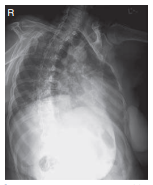

What projection/position is this?

Left Lateral Decubitus (AP)